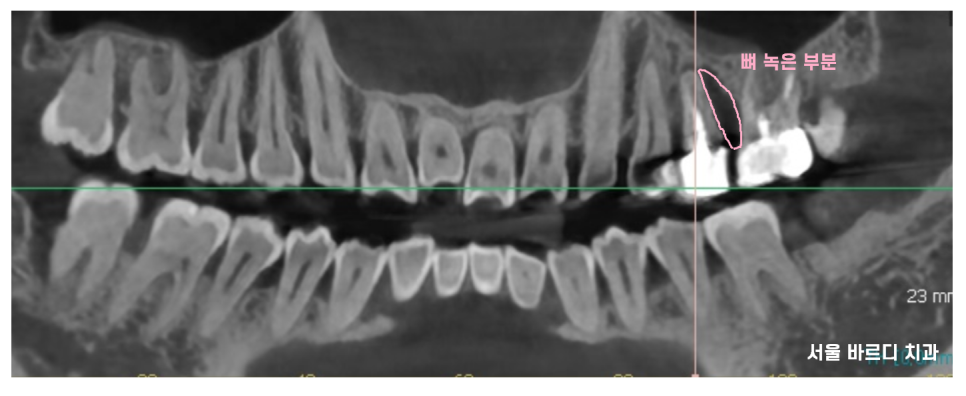

22.12.14

ct를 찍어보았는데

왼쪽 위에 문제 치아가

뼈가 많이 녹았습니다.

언제 치료했는지도 모르겠어요~~

말씀해주셨는데요.

보철 부분이 닳아서

안쪽 부분이 다 들어날정도로 오래 쓰셨어요.